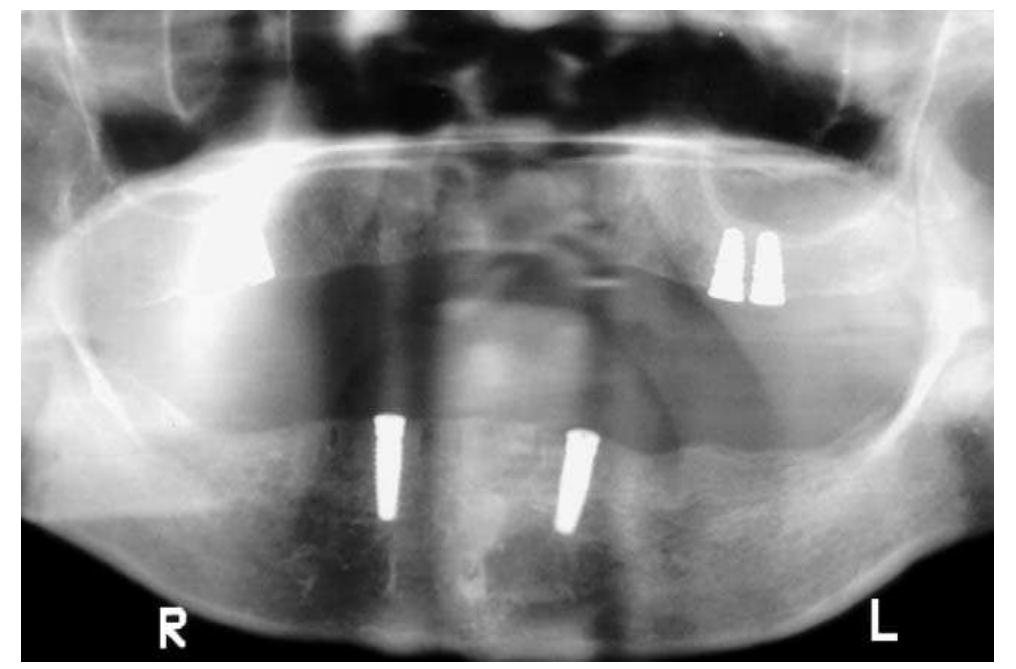

Limited oral access presents a unique challenge to prosthodontic treatment. An edentulous patient who developed microstomia after a maxillary lip resection is presented. The clinical procedure and the rationale for the treatment approach... more